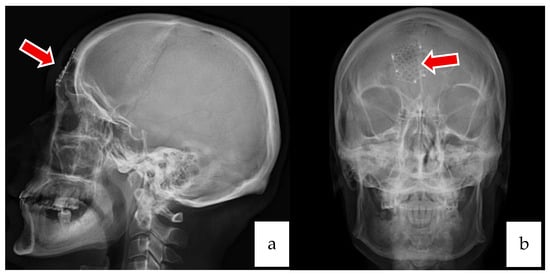

2.1. Case 1